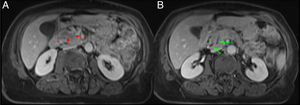

En la RM, la afectación inflamatoria laminar en el surco PD se identifica como una hipointensidad de señal en secuencias T1, con intensidad de señal heterogénea en secuencias T2 y STIR (figs. 5 y 6). Dicha afectación inflamatoria presenta un realce parcheado y progresivo tras la administración de contraste debido a su contenido fibrótico7,9. En fases agudas, la afectación inflamatoria en el surco PD suele presentar una mayor intensidad de señal en la secuencia T2 por presencia de edema y líquido que, progresivamente, se transforma en tejido fibrótico en fase subaguda/crónica y en secuencias T1 y T2 presenta una menor intensidad de señal debido a la atrofia parenquimatosa y la fibrosis. Por tanto, la secuencia T2 resulta muy útil para inferir el grado de actividad7.

Mismo caso que la figura anterior. Cortes axiales del abdomen en secuencias T2. A) Dilatación de la vía biliar intra- y extrahepática y del conducto pancreático principal en cuerpo y cola del páncreas, con afilamiento del conducto pancreático principal en la cabeza pancreática (flechas verdes). B) Lesiones hiperintensas en la pared medial del duodeno que corresponden con lesiones quísticas (flechas rojas) con borramiento del surco pancreaticoduodenal (asterisco rojo).

Varón de 48 años con historia de alcoholismo y pancreatitis aguda de repetición. Cortes axiales del abdomen en secuencias T2. A) Dilatación del conducto pancreático principal (flecha verde). B) Borramiento de los planos grasos del surco pancreaticoduodenal y pequeñas imágenes de aspecto quístico en pared duodenal (flechas rojas). Estos hallazgos, dado el antecedente del paciente, son compatibles con pancreatitis del surco.

En ambos subtipos de PS, el aspecto medial del duodeno se encuentra engrosado con múltiples quistes en el interior de su pared y en el surco, que se identifican como focos hiperintensos en secuencias T2 (figs. 5 y 6)7. Algunos autores defienden que estos quistes intramurales del duodeno son islotes pancreáticos heterotópicos o incluso ramas ductales del conducto de Santorini dilatadas1.